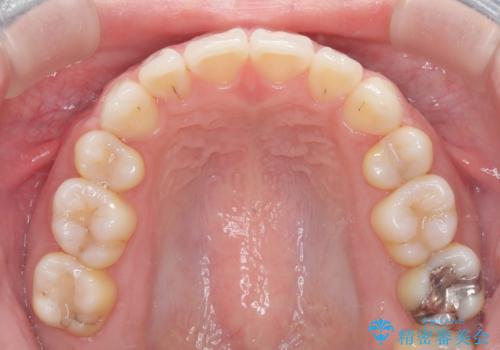

- 治療計画

上下左右の第一小臼歯を抜歯し、クリアブラケット(白い装置)とメタルワイヤーを使用して矯正を開始。初期には犬歯のアーチ内への整列を優先し、中盤からは前歯と奥歯の咬合関係の調整を進めました。審美性に優れた装置を使用したことで、治療中も目立ちにくく、見た目へのストレスが少ない点も評価されています。全体の治療は1年半で完了し、見た目・噛み合わせともに大きく改善。患者本人も「短期間でここまで変わるとは思わなかった」と満足されていました。